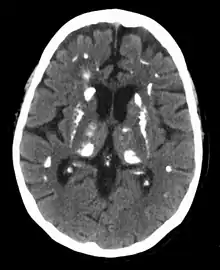

Hyperparathyroidism can cause hyperchloremia and increase renal bicarbonate loss, which may result in a normal anion gap metabolic acidosis.[32] ALP level can be elevated due to bone turnover. Additionally further tests can be completed to rule out other causes and complications of hyperparathyroidism including a 24-hour urinary calcium for familial hypocalciuric hypercalcemia, DEXA scan to evaluate for osteoporosis, osteopenia, or fragility fractures, and genetic testing.[33][34][35][36] Additionally a CT scan without contrast or renal ultrasound can be done to assess for nephrolithiasis and/or nephrocalcinosis if there is concern for it.[36]